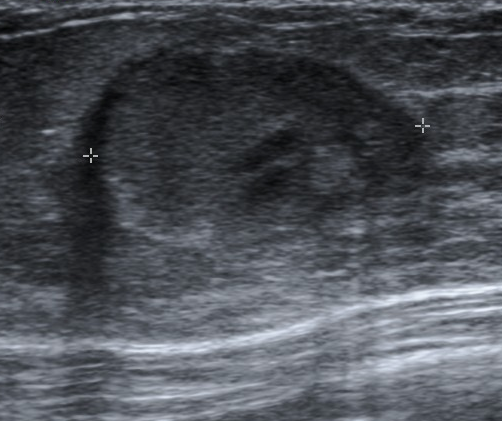

Galactocele on ultrasound

Galactocele on ultrasound. Source: Radiopaedia. Galactocele [9]

2. Breast ultrasound: allows visualization of non-echoic fluid-filled, avascular cystic mass;

On ultrasound, a galactocele is visualised as a typical cystic mass. The key ultrasound signs are: a non-echoic structure (fluid-filled), clear even contours, and no blood flow within the mass on Doppler imaging (avascularity).